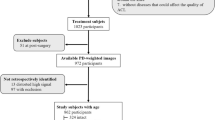

A total of 1922 articles were initially retrieved for this meta-analysis: 481 from PubMed, 783 from EMBASE, 470 from Ovid, 129 from BIOSIS Previews, 53 from the Cochrane library and 6 articles obtained from manual retrieval of relevant references by sending e-mails to authors. 759 reports were then eliminated out of 1232 duplicated reports as they originated from the same team or the same set of data. According to the inclusion and exclusion criteria for the initial screening, a total of 110 articles were thus selected after reading the title and abstract (71 from PubMed, 24 from EMBASE, 11 from Ovid and 4 from the Cochrane library) and the articles were marked with 1 star in EndNote software. By evaluating the full text, two researchers (K.L. and J.D.) then selected 31 papers that strictly complied with the inclusion and exclusion criteria and marked them with 2 stars in EndNote. Ten studies were excluded after re-assessing the full text during the third screening. Finally, 21 articles9, 14,15,16,17,18,19,20,21,22,23,24,25,26,27,28,29,30,31,32,33 were chosen and marked with 3 stars, articles for which true positive (TP), false positive (FP), true negative (TN) and false negative (FN) results could be extracted or accurately calculated through 2 × 2 contingency tables (16 from PubMed and 5 from EMBASE). These articles consisted of 16 prospective studies and 5 retrospective studies, for a total of 1722 cases. The literature search, the screening process and the results are shown in Fig. 1. The basic characteristics of the studies which were included are displayed in Table 1. From a chronological point of view, 38% (8/21) of these studies were published between 2006–2009 inclusive and 62% (13/21) in the period 2012–2016.

Flow of information through the different phases of the meta-analysis. From: Moher, D., Liberati, A., Tetzlaff, J. & Altman, D. G. Preferred reporting items for systematic reviews and meta-analyses: the PRISMA statement. PLoS medicine 6, e1000097, doi:10.1371/journal.pmed.1000097 (2009).